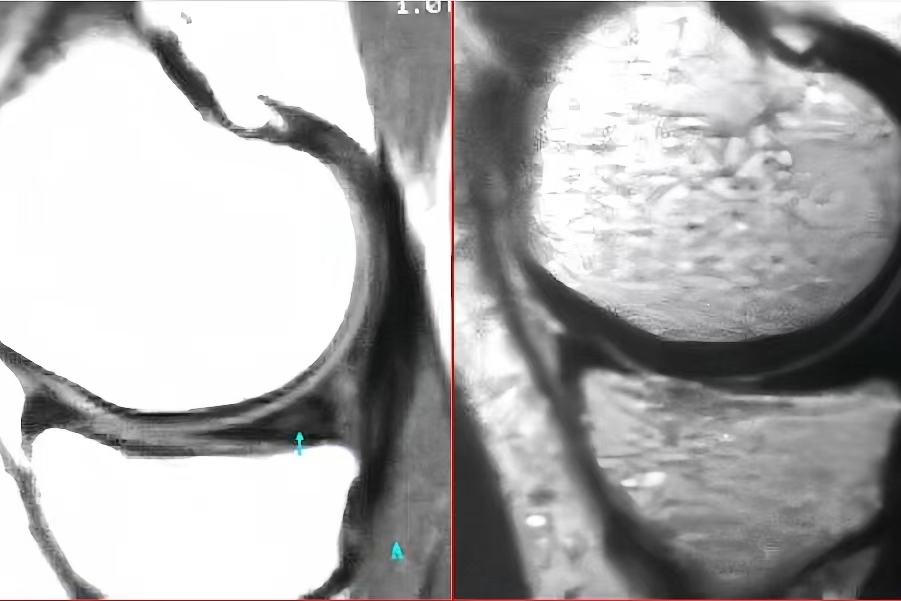

王月英,女,46岁,20183456,左膝内侧半月板损伤